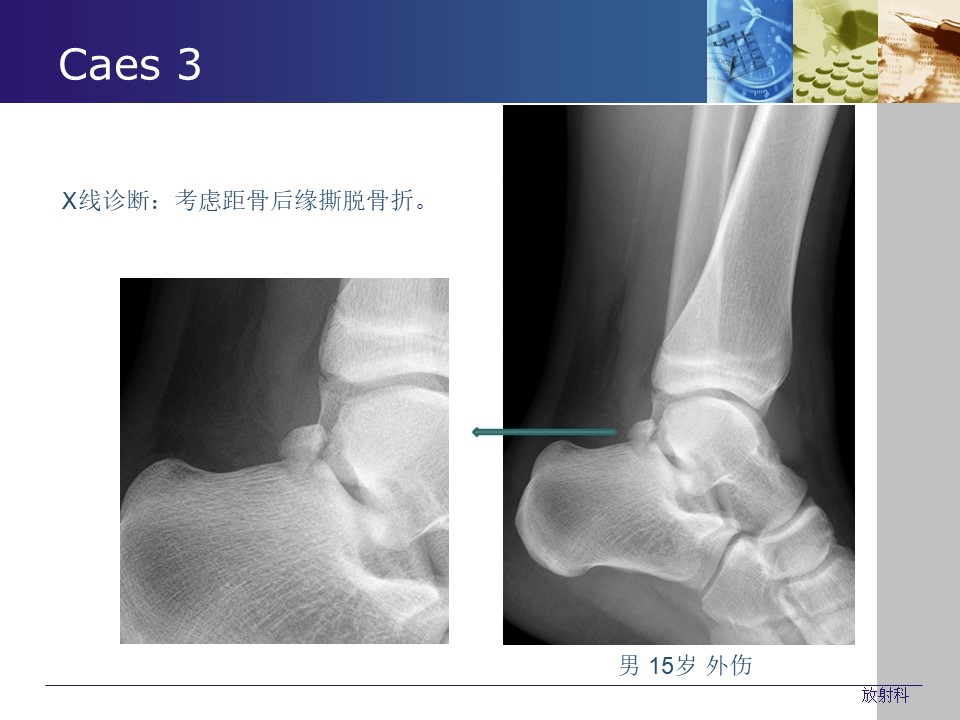

“常见生理(解剖)变异与撕脱骨折的影像学鉴别PPT” 的相关文章